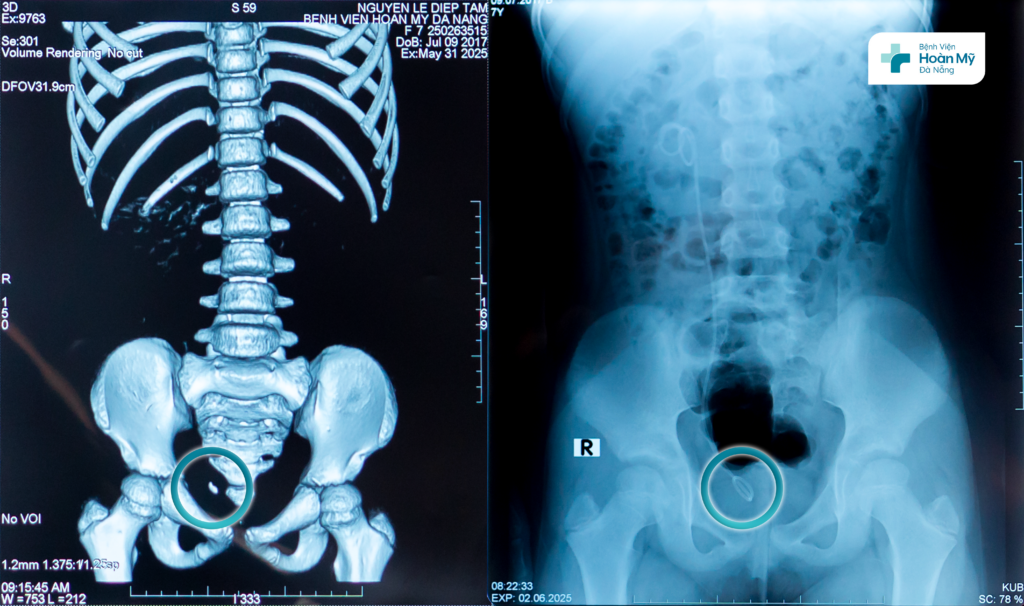

Bé N.T.Tâm (8 tuổi, trú tỉnh Quảng Nam), đau quặn hông phải nhiều được mẹ đưa đi khám và được chẩn đoán sỏi niệu quản phải 1/3 dưới, điều trị nội khoa nhiều đợt ở các bệnh viện khác nhau nhưng không hiệu quả.

Đầu tháng 6/2025, gia đình đưa trẻ đến Bệnh viện Hoàn Mỹ Đà Nẵng khám và tìm kiếm phương pháp điều trị cho con. Sau thăm khám, siêu âm, chụp CT liều thấp chẩn đoán, các bác sĩ quyết định lựa chọn phương pháp tán sỏi ngược dòng nhằm loại bỏ viên sỏi, đồng thời đảm bảo an toàn, thẩm mỹ cho trẻ.

Bệnh nhi sạch sỏi niệu quản sau điều trị nội soi tán sỏi ngược dòng

2 ngày sau phẫu thuật, trẻ đã ổn định, hết đau, dòng tiểu thông thoáng, kiểm tra trên phim thấy sạch sỏi và có thể xuất viện về nhà.